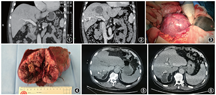

男性,65岁,因“右上腹痛10余天,发现右肝巨大占位”于2018年10月8日入院。患者10余天前无明显诱因出现右上腹中等程度疼痛,呈持续性,不伴发热、恶心、呕吐。外院超声检查结果提示肝脏右叶巨大实性占位,考虑为巨块型肝癌。既往否认高血压病、糖尿病、肝炎、结核等病史,否认药物、食物过敏史。入院体检:腹平软,右上腹肋缘下可触及肝脏肿大,下缘位于肋下4 cm,肝区轻度叩痛。甲胎蛋白56.05 μg/L,癌胚抗原5.89 μg/L。ALT 85 U/L,AST 83 U/L,胆红素正常。乙肝表面抗原、丙肝抗体均阴性。腹部CT增强扫描示肝脏5、8段巨大实性肿物,大小约11.3 cm×7.2 cm×8.7 cm,考虑为肝细胞癌,周围未见转移结节(图1)。PET-CT示右肝巨大占位,考虑恶性肿瘤,其余肝脏、腹腔及全身均未见转移。吲哚菁绿15 min潴留率为13.4%。

患者于2018年10月15日行门静脉右支栓塞+经动脉栓塞化疗术,术中分别经肝穿刺栓塞门静脉右前支及右后下支,并经肿瘤供血动脉注射吡柔比星20 mg和栓塞微球。治疗后患者无发热,经保肝、胸腺法新(1.6 mg,2次/周)免疫调节治疗3周后,复查血甲胎蛋白13.26 μg/L,癌胚抗原3.97 μg/L,肝功能正常。CT增强扫描示:肝脏5、8段肿物,最大径9.8 cm,内部坏死,病变侵入左肝管,继发左叶胆管扩张;病变压迫右肝管可能,不除外受累,继发远端肝右叶胆管轻度扩张;肝尾叶及左肝体积较前略增大(图2)。吲哚菁绿15 min滞留率为7%。经过第二次多学科综合治疗协作组讨论,于2018年11月15日在全身麻醉下行根治性右半肝切除+胆管空肠Roux-en-Y吻合术。术中见肝脏右前叶巨大肿瘤(图3, 4),右肝管及肝总管内可及癌栓并向左肝管内突出,行右半肝切除并切除肝外胆管及部分左肝管,左肝管与空肠行Roux-en-Y吻合术。术后病理学检查示:右半肝低分化肝细胞癌,伴大量出血及坏死,肿瘤大小为7.6 cm×5.2 cm×4.8 cm,肿瘤未侵犯肝被膜,可见近瘤旁微血管侵犯灶(M1,低危组),病变紧邻肝手术切缘,胆管断端净,肝门区淋巴结未见转移。术后恢复顺利,围手术期使用注射用胸腺法新(1.6 mg,1次/d)免疫调节治疗。术后复查甲胎蛋白6.63 μg/L,癌胚抗原2.08 μg/L。患者于术后13 d出院。

出院后开始皮下注射胸腺法新(1.6 mg,2次/周)。术后1个月开始口服仑伐替尼(8 mg,1次/d),静脉注射帕博利珠单抗(200 mg,1次/3周,共6次,末次用药时间为2019年4月23日)。术后2个月复查腹部CT示:肝脏未见异常强化灶(图5)。术后5个月CT示:肝实质未见异常强化,肝脏右后切缘囊性灶,较前新发(图6);复查甲胎蛋白5.25 μg/L,癌胚抗原13.56 μg/L;PET-CT示:肝脏右后缘低密度灶,边缘不规则增厚,葡萄糖代谢环形增高,考虑复发可能大;左侧髂骨低密度灶葡萄糖代谢增高,考虑为骨转移。